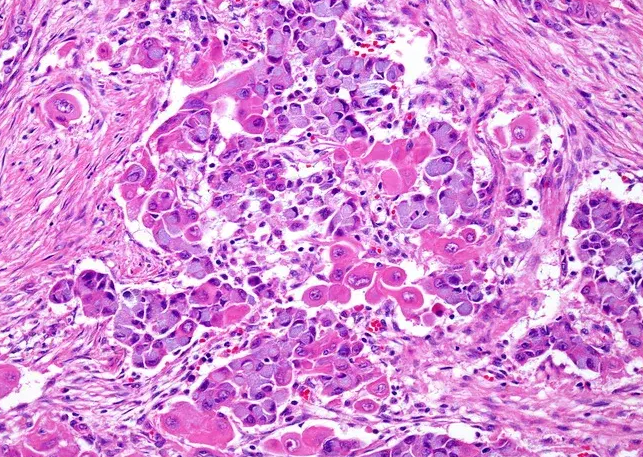

Mucinous cells with blue cytoplasm and flattened nuclei, intermixed with squamous cells containing dense eosinophilic cytoplasm and round nuclei. Courtesy Dr. V. Penopoulos.